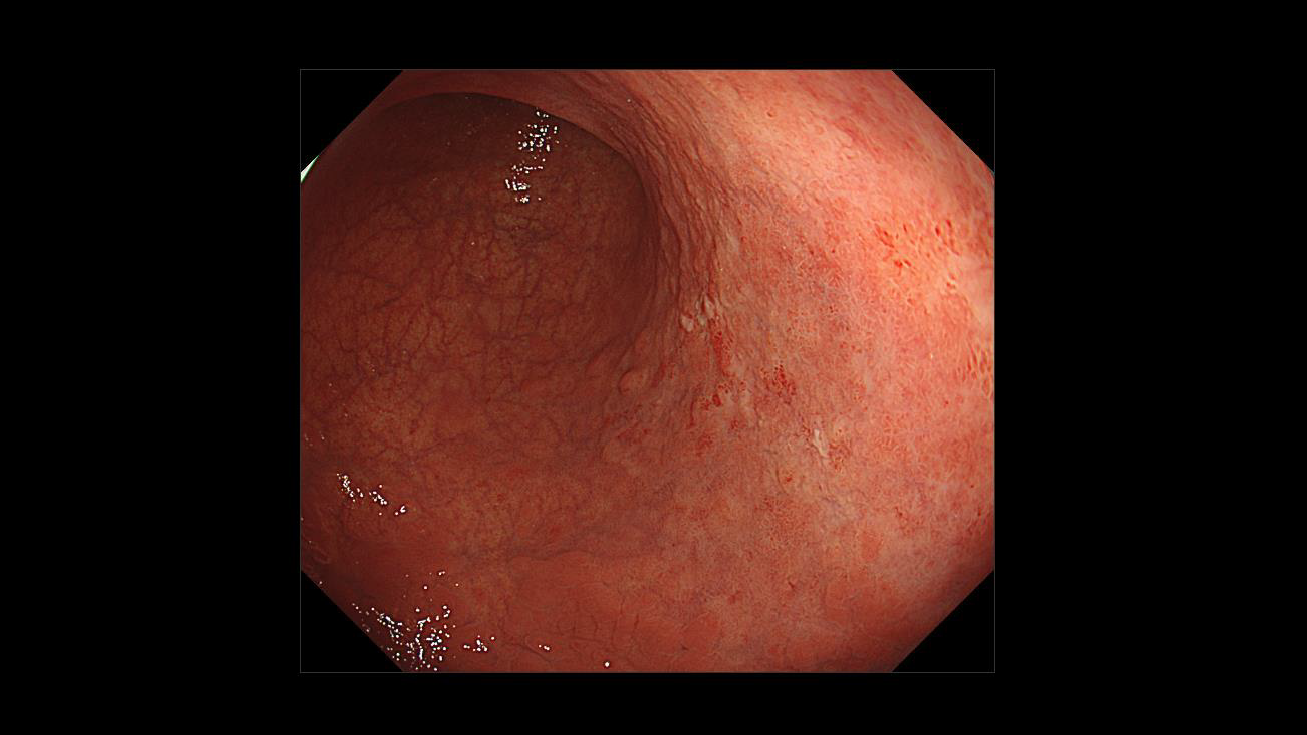

ホーム > 診療科・部門案内 > 消化器センター 消化器内科 > 消化管Mapping > 消化管Mapping~胃~ > 消化管Mapping~胃~ 2025.9.10